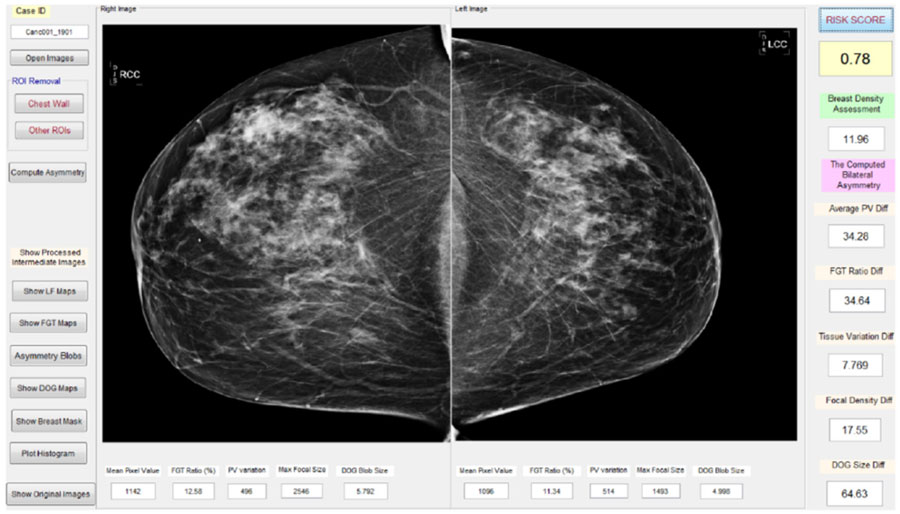

最近,郑教授和他的团队鉴定并根据双侧乳腺X射出密度和组织不对称的定量分析确定并调查了新的短期乳腺癌风险因子或预测模型。几项研究(即[8])已经证明,使用这种新模型具有增加歧视性能以预测短期乳腺癌风险,从而有助于提高乳房X线摄影筛查的疗效。